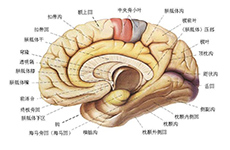

严重颅脑损伤、多发伤、复合伤

疾病介绍:严重颅脑损伤、多发伤、复合伤,多为交通、工矿事故、自然灾害、爆炸、火器伤、坠落、跌倒以及各种锐气、钝器对人体伤害。除正确诊断和及早手术外,加…【详细】